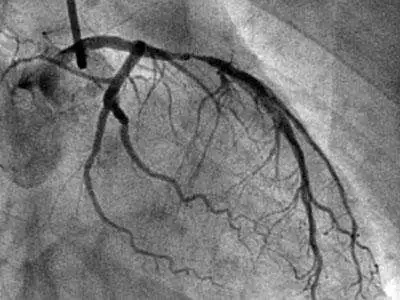

心脏冠脉造影就是给心脏的冠状动脉进行造影成像分析,是诊断冠状动脉粥样硬化性心脏病(冠心病)的一种常用且有效的方法,较为安全可靠,现广泛应用于临床,被认为是诊断冠心病的“金标准”

冠脉造影的方法是从手腕处的桡动脉或大腿处的股动脉的人为切口处,插入一根导管,并沿行到心脏的冠状动脉开口处,并把造影剂(在X光下显影)注入冠状动脉,然后利用X光对冠脉造影成像,这样冠状动脉内部的形态就可以显示出来。

心脏冠脉造影可供医生判断冠脉有无狭窄、斑块等,了解冠脉的内部形态及血流速度。